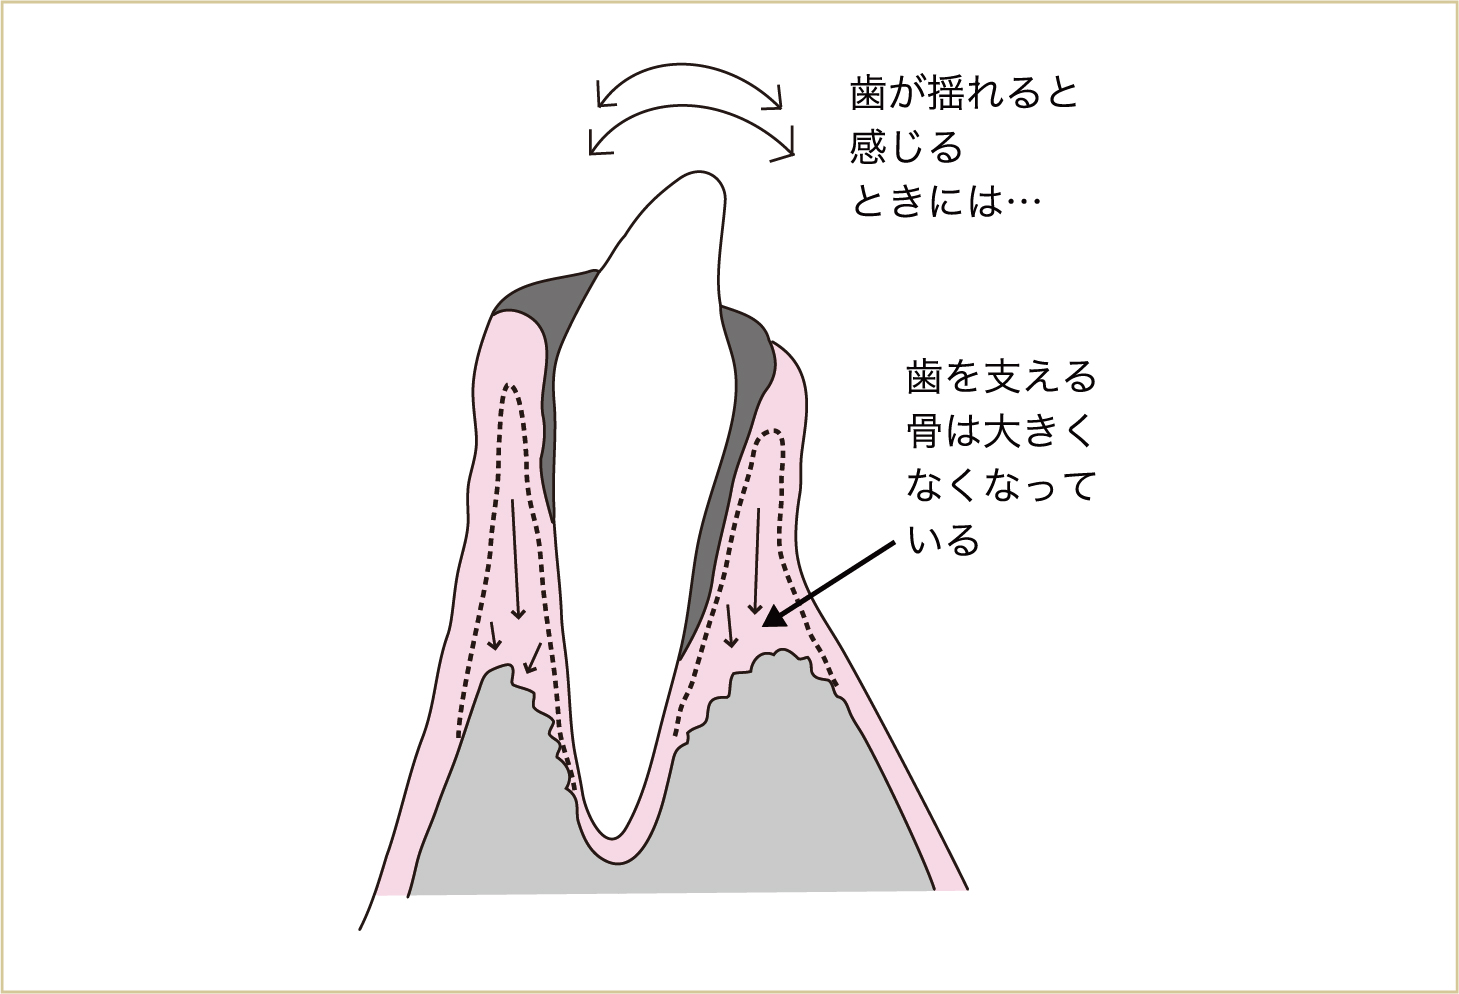

この反応が歯周炎です。つまり、歯周病とは歯を支える骨が壊れることなのです。 歯を支える骨が壊れはじめると、プラークはこの壊れた部分、骨がなくなった部分にまで侵入してきます。これが繰り返されて、歯を支える骨が大きくなくなると、歯はグラグラと動揺してきます。

さらに病状が進行すると、細菌による毒素は、歯肉だけでなく、歯を支える骨や歯根表面にまで悪影響を与える。その結果として、歯を支える骨が壊れていく。

歯周病とは、歯を支える骨を壊す病気である。